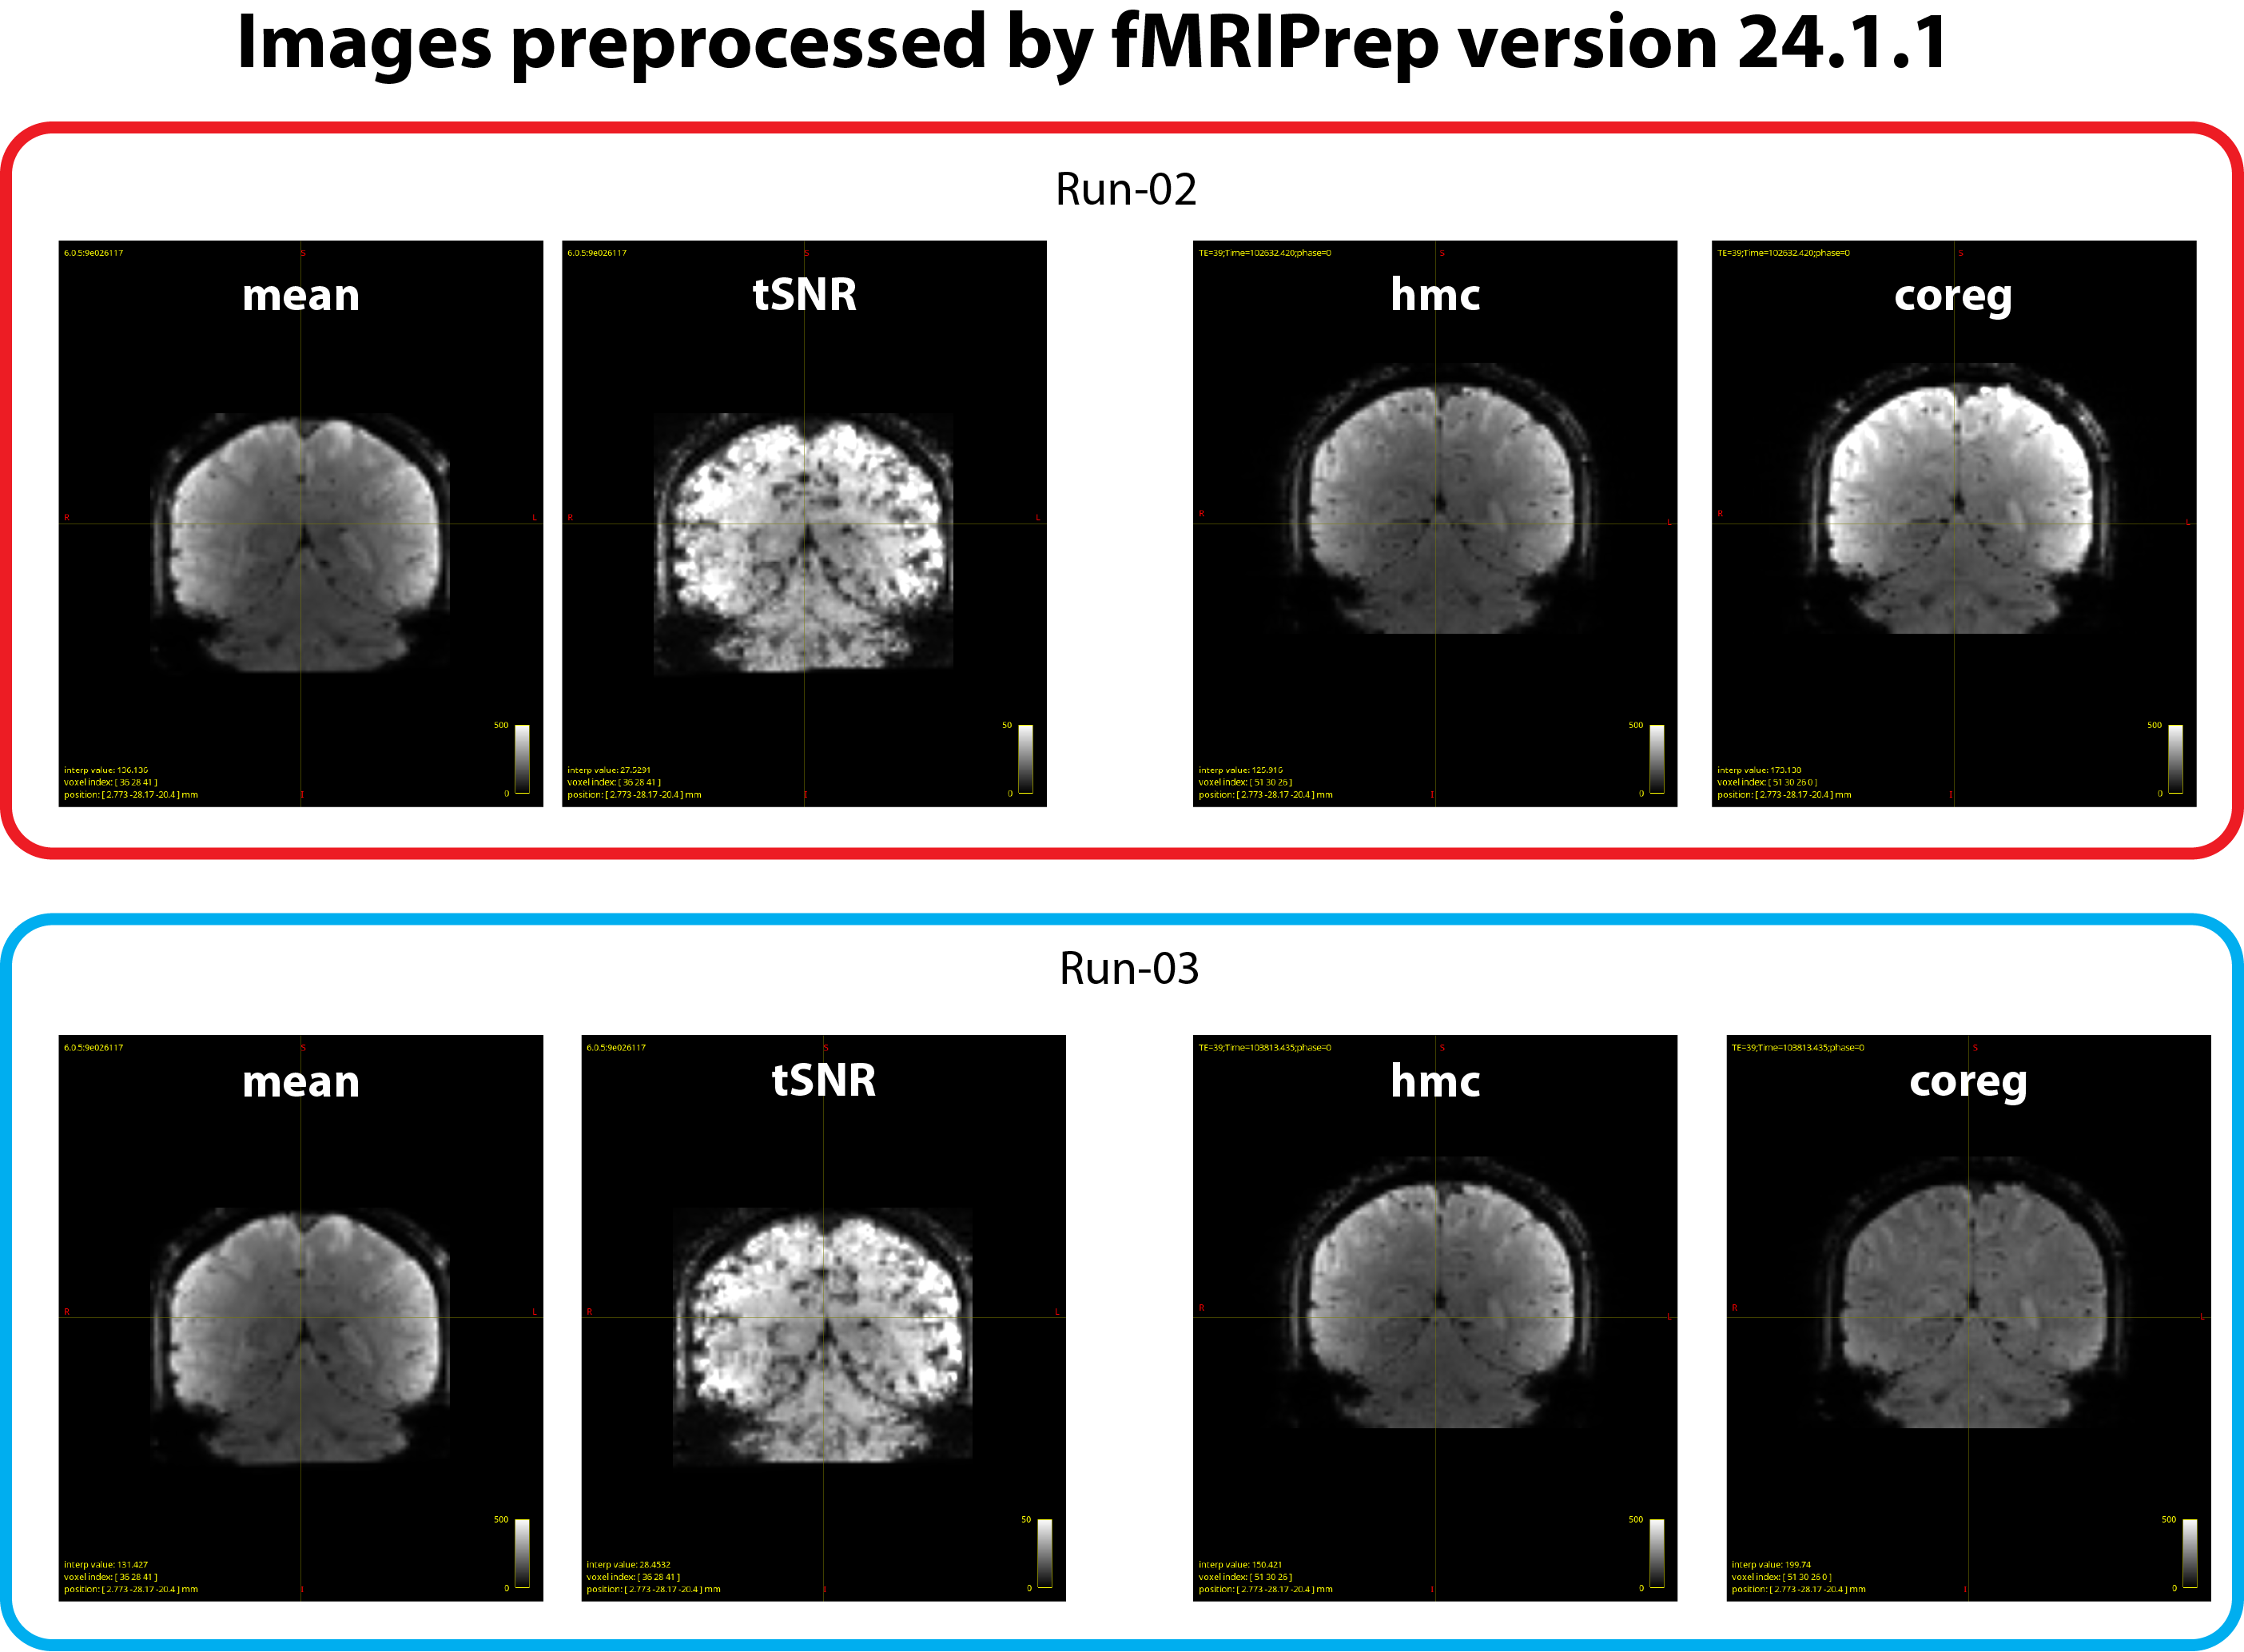

The issue is that the image intensity of the *_desc-coreg_boldref.nii.gz files is inconsistent across runs. As we understand, this image is used for coregistration to the T1-weighted image, and a bias-field correction is typically applied to improve alignment. However, this correction seems to succeed in some runs (e.g. run-03 in our case) but not others (e.g. run-02 in our case), resulting in marked intensity differences across runs. We have attached example images illustrating the issue (see figure 2 below). This phenomenon occurred with fMRIPrep v24.1.1, and runs showing this inconsistency also yield weaker or absent BOLD z-score signals in the GLM results.

- tSNR maps look similar across runs (see figure 1 and 2).

*_desc-hmc_boldref.nii.gzimages (generated just before the coregistration step) are also consistent (see figure 2).

Thus, the inconsistency seems to arise at the *_desc-coreg_boldref.nii.gz step.